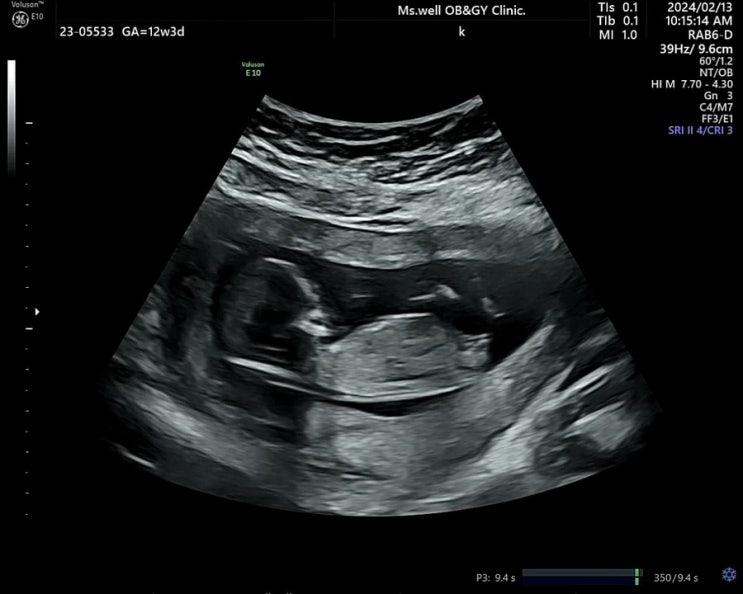

초기입체초음파, 1차 기형아검사, 임신중독증 검사 (9주 ~ 12주)

9주 4일 피고임에 좋다는 연근가루 구매해서 하루에 한잔씩 타 먹었는데 확실히 피가 덜 나왔다. 거의 안나...